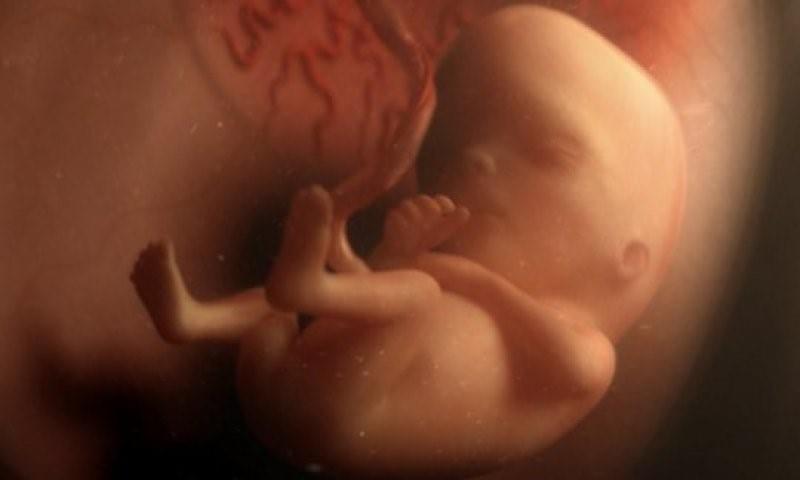

В течение трех недель клетки образуют малюсенький шарик (эмбрион). Формируются первые нервные клетки. После восьмой недели и до рождения будущего ребенка правильно называть плодом.

Вокруг плодного яйца образуется водонепроницаемая оболочка с жидкостью (амниотический мешок), защищая растущий эмбрион. Одновременно развивается плацента – округлый плоский орган, через который плод получает питательные вещества от матери.

На лице эмбриона появляются большие темные круги вместо глаз, рот, нижняя челюсть и горло. Клетки крови обретают форму, и запускается кровообращение. К концу четвертой недели сердце уже бьется 65 раз в минуту.

На голове появляются небольшие складки кожи в районе ушей, глаза. Формируются крошечные ручки, ножки, пальцы.

Полная сформирована нервная трубка (головной, спинной мозг и другие элементы центральной нервной системы). Начинают развиваться пищеварительный тракт и органы чувств. Хрящи заменяются костями.

Появляется сердцебиение, а голова ребенка гораздо больше по отношению к остальному телу.